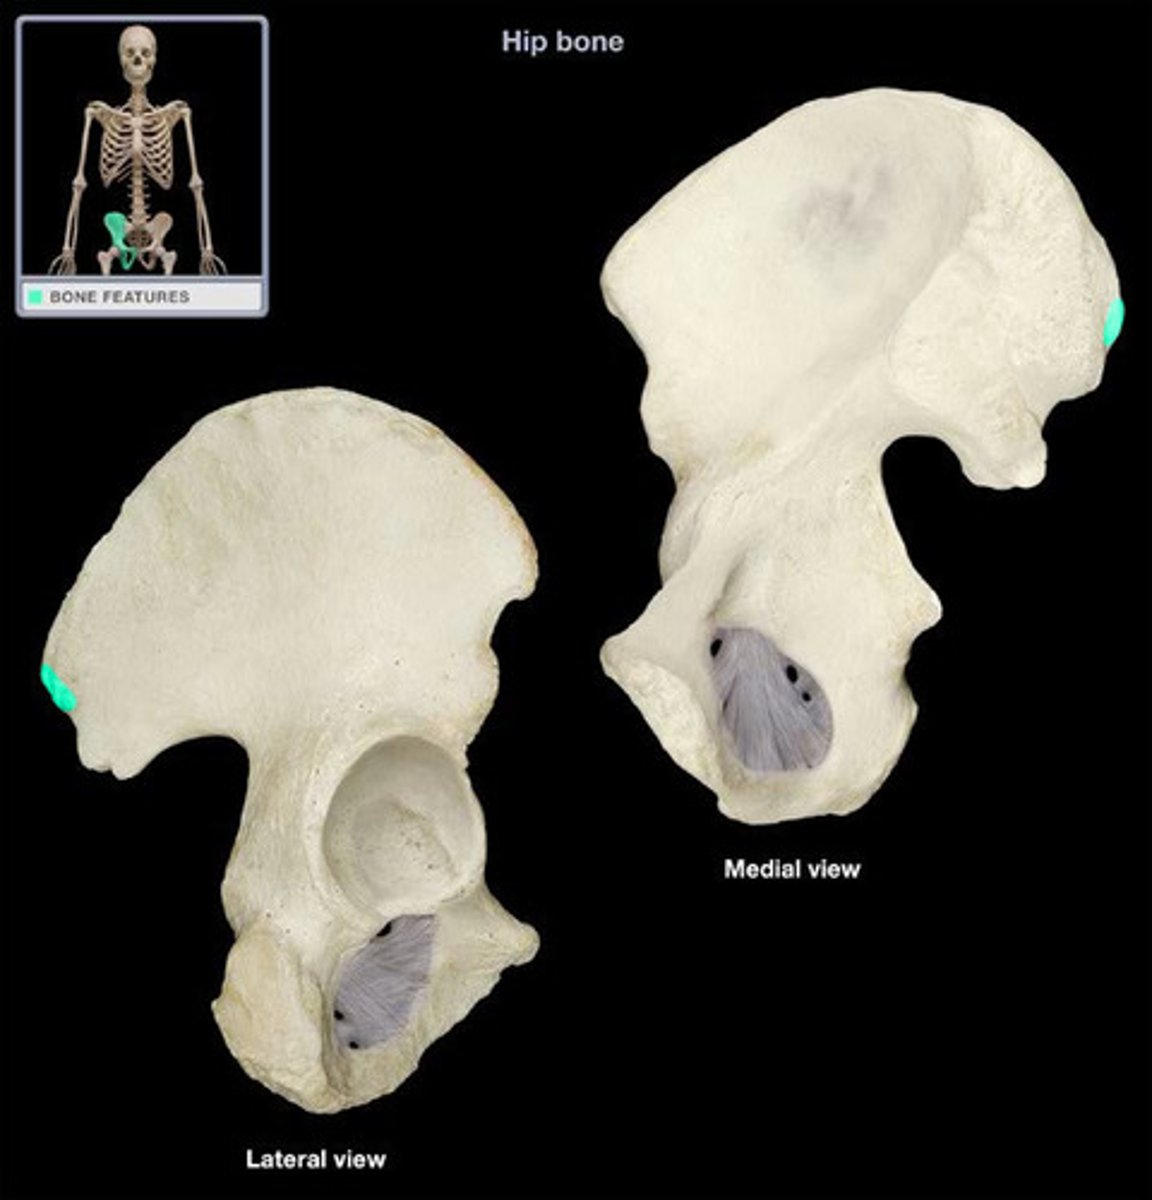

ox coxae

hip bones

3 bones fused together, anteriorly connected at the pubic symphysis and posteriorly at the sacrum

ilium

weight bearing during sitting

pubis

The medial anterior portion of the pelvis

ischium

the lower, posterior portions of the pelvis

iliac crest

upper margin of iliac bones

posterior superior iliac spine

the sharp posterior end of the iliac crest

posterior inferior iliac spine (PIIS)

a bony projection located inferior to the posterior superior iliac spine

anterior superior iliac spine

origin of sartorius

anterior inferior iliac spine (AIIS)

origin of rectus femoris

iliac fossa

The broad, slightly concave inner surface of the ilium.

Acetabulum

large socket in the pelvic bone for the head of the femur

acetabular notch

deep notch in the inferior part of the brim

greater sciatic notch

allows blood vessels and the large sciatic nerve to pass from the pelvis posteriorly into the thigh

ischial tuberosity

receives the weight of the body when sitting

body of ischium

Makes up all of the ischium superior to the tuberosity

ramus of ischium

joins the inferior ramus of the pubis anteriorly

obturator foramen

opening in hip bone formed by the pubic and ischial rami

body of pubis

origin of adductor longus

arcuate line

a ridge of bone that runs inferiorly and anteriorly from the auricular surface, forms pelvic brim

iliopubic eminence

marks the point of union of the ilium and the pubis just lateral to the arcuate line

pubic tubercle

An attachment point for the inguinal ligament.

superior ramus of pubis

origin of pectineus

inferior ramus of pubis

origin of adductor brevis